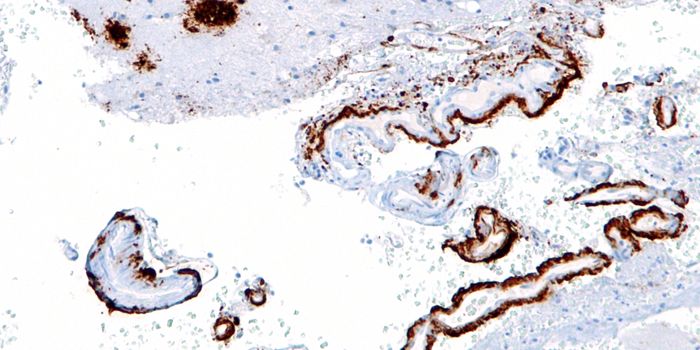

JUN 08, 2016NeuroscienceIt’s been known for a while that plaques of the protein amyloid beta are part of the pathology of Alzheimer’ ...

MAY 11, 2016ImmunologyThe brain’s immune system potentially could be harnessed to help clear amyloid plaques, which are a hallmark of Al ...

APR 05, 2016NeuroscienceAlzheimer’s Disease (AD) is the most common form of dementia, currently affecting 5.5 million people in the U.S. T ...

OCT 12, 2015NeuroscienceAlzheimer’s disease and other forms of dementia are estimated to grow exponentially over the next five decades. In ...